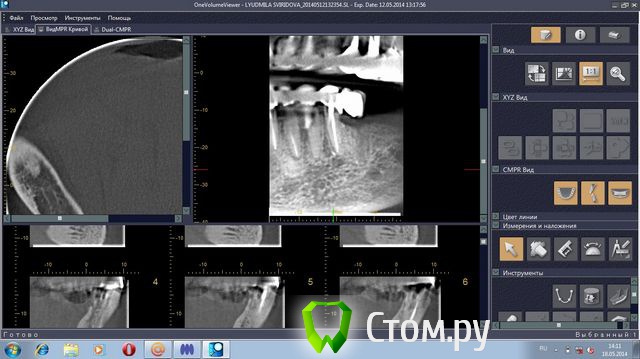

stradalitca Опубликовано 18 мая, 2014 Поделиться Опубликовано 18 мая, 2014 Здравствуйте! у меня проблема такая. за последние 4 года мне удалили нижний центральный зубик (киста была), пролечили каналы в нижних зубах. Поставили мост с металлокерамики. Он простоял некоторое время, а потом( год-два) просто стал качаться. Его раза три сажали заново на цемент( прошлым летом). в итоге, пошла в другую клинику. Мост ещё раз сняли( он держался на честном слове). Оказалось, что пятёрка снизу слева пробита вкладкой. Зуб удалили. На сдедующий день обточили ещё зубы некоторые и сняли слепок под новые пару вкладок. через неделю поставили на цемент( сразу на цемент, без времянки)НОВЫЙ мост. Это было в конце декабря. Через две недели десну разнесло и прищлось резать, выпускать гной( надрез примерно под тройкой слева). Сейчас опять явный свищ примерно под 3-4 нижними слева.Сделали рентген - оказалось, что тройка имеет два корня и она пробита вкладкой. Теперь даже не знаю что делать. Просто резать десну и опять чистить? Врач говорит, что надо снять мост и удалить тройку. Другой врач говорит, что тройку может и можно спасти, надо снять мост, убрать вкладку и смотреть, что с тройкой. На прошлой неделе сделала объёмный рентген. Сама неделю копалась в программе, разглядывя свою нижнюю челюсть. мне показалось, что там маячит какой-то остаток корня шестёрки слева( мне его сто лет назад удаляли). Пожалуйста, подскажите, что делать? какие перспективы и варианты есть на мои нижние зубы?Заранее большое спасибо за все ваши ответы и мнения.Скриншоты с программы 3D прилагаю.или может надо мост снять, выдернуть тройку слева и поставить металлопластмассу?( верхние зубы тоже штук 8 слитно металлокерамика, ставили первый паз отдновременнно нижние и верхние) Ссылка на комментарий

sydnik Опубликовано 18 мая, 2014 Поделиться Опубликовано 18 мая, 2014 Здравствуйте! скриншоты не очень информативные,носкажу наверняка -3-ку на удаление, разрезами десны и чистками ничего не добьетесь.корня шестерки я не вижу.металлопластмассу не рекомендовал бы( синеет,откалывается,стирается,эстетика хромает на обе ноги). Мост расшатался из-за отсутствия зубов слева, в результате чего вся нагрузка ушла на передние зубы имплантацию не рассматривали?все ли хорошо с верхним мостом? пока все Ссылка на комментарий